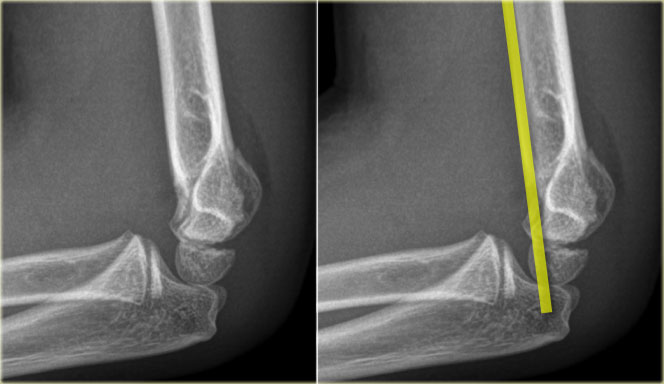

Anterior humeral line.

A line drawn on a lateral view along the anterior surface of the humerus should pass through the middle third of the capitellum..

This line is called the Anterior Humeral line .

In cases of a supracondylar fracture the anterior humeral line usually passes through the anterior third of the capitellum or in front of the capitellum due to posterior bending of the distal humeral fragment.

On the left the anterior humeral line passes through the anterior third of the capitellum.

This indicates that the condyles are displaced dorsally (i.e. supracondylar fracture).